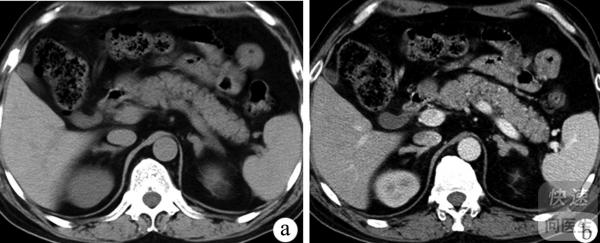

核心提示:谁都想拥有一个健康的身体,但是不是每一个人都可以拥有的,因为生活当中只要我们稍微不注意一下,我们就有可能出现某种健康问题,比如有一些人因为某种原因导致自己肾上腺增生。如果有人出现这种情况的话,那么这些人...